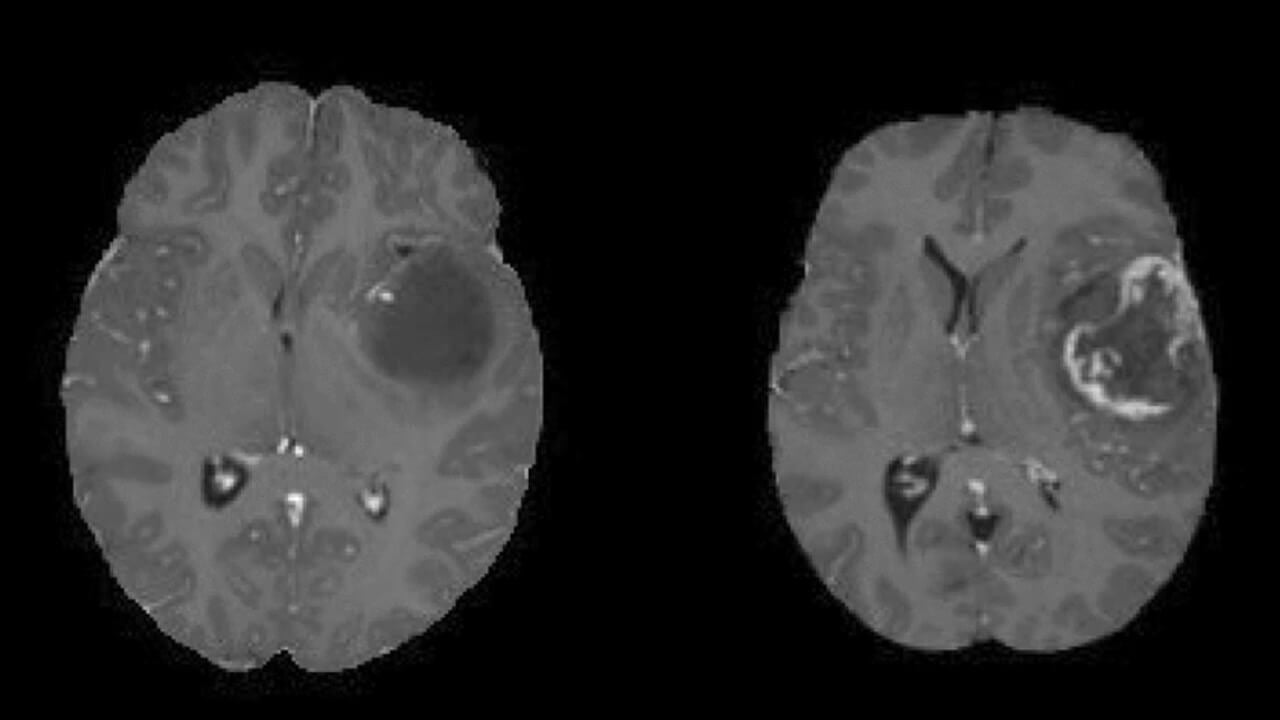

Virtually every cell in the brain can be the origin of a tumor. Nevertheless, some cells, such as neurons, are less likely to form a tumor because they don`t divide. Other cells, such as those of blood vessels or the pituitary gland, are more physiologically active and thus can be the structural basis of a tumor. The cell type determines the tumor's location, the rate of its growth, and its ability to produce excessive amounts of hormones. The diagnosis often relies on an MRI for a benign brain tumor.

- Neuronavigation systems. It is a modern, important part of any neurological procedure that integrates preoperative MRI or CT scans to create a 3D map of the brain. It helps surgeons precisely plan the surgical path, avoid critical structures, and improve the accuracy of neoplasm removal.